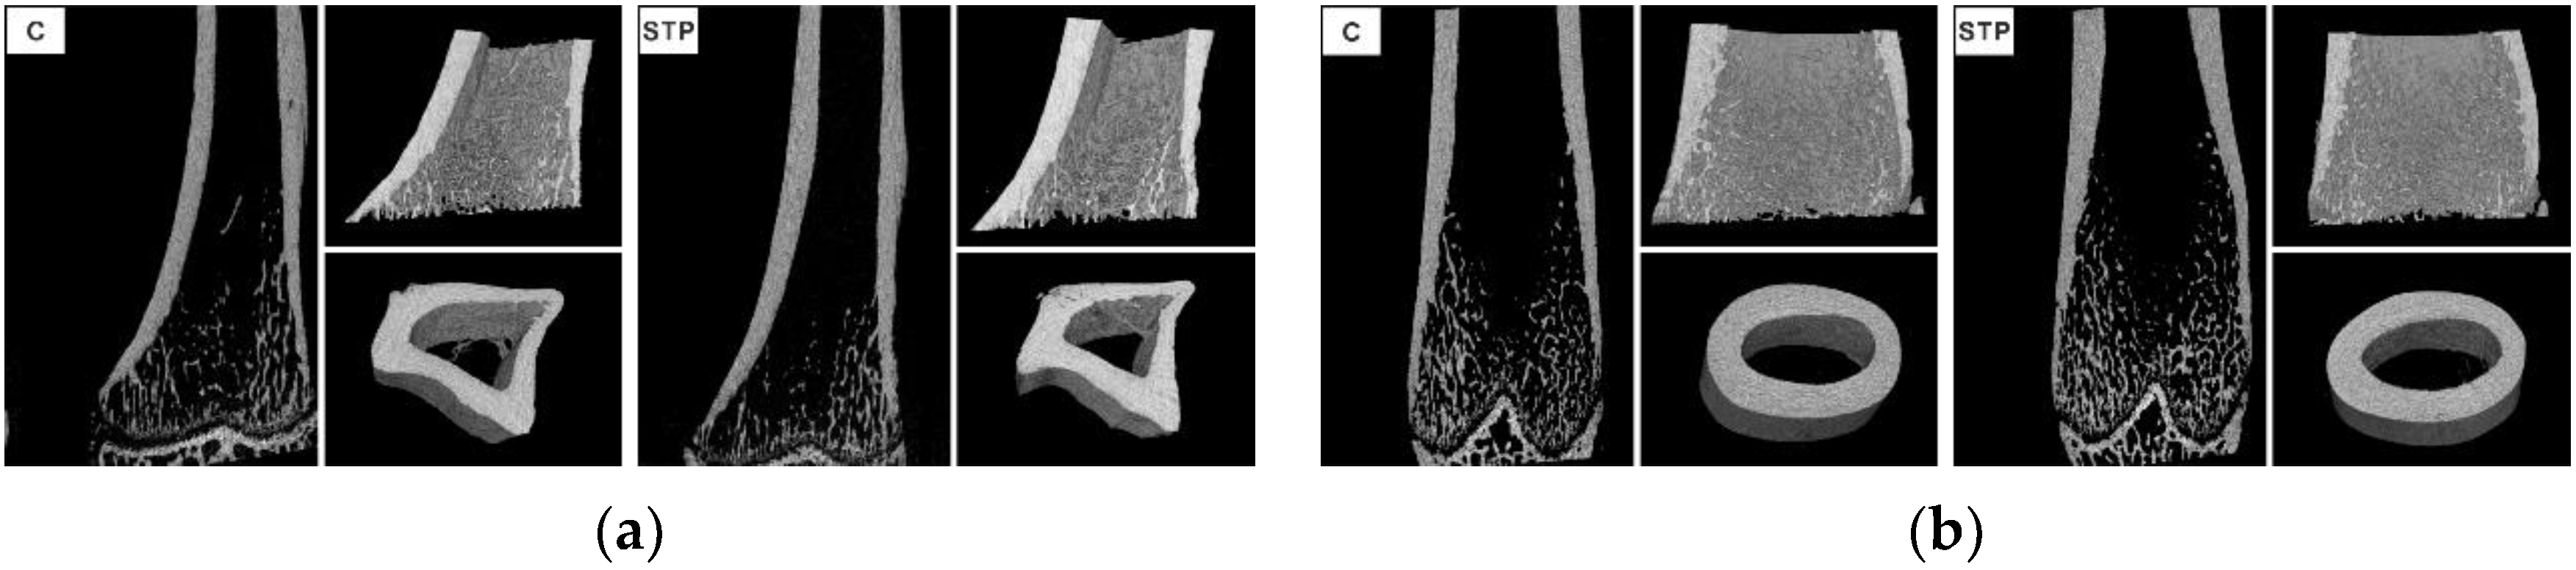

2.5. Micro X-ray Computed Tomography

- Bouxsein, M.L.; Boyd, S.K.; Christiansen, B.A.; Guldberg, R.E.; Jepsen, K.J.; Muller, R. Guidelines for assessment of bone microstructure in rodents using micro-computed tomography. J. Bone Miner. Res. 2010, 25, 1468–1486. [Google Scholar] [CrossRef] [PubMed]